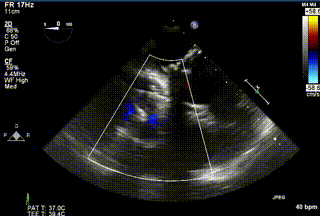

患者一术前心超

患者一术后心超